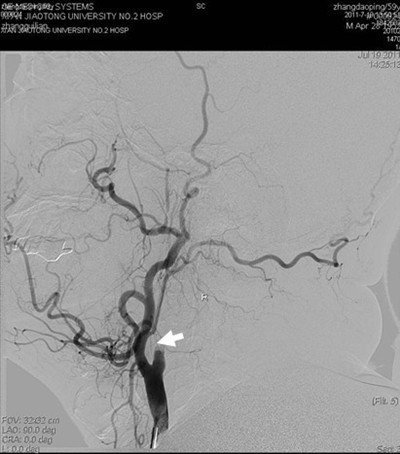

(图1) 造影见左侧颈内动脉开口附近闭塞(箭头所示),颅内血管未显影

患者张某,59岁,以左侧肢体活动不灵14天入院,14天前患者突然出现左侧肢体无力,活动受限,并言语含糊,曾于外院就诊,脑CT及MR提示脑梗死,治疗后效果不明显,遂来我院。既往有高血压史数年,长期间断服降压药。入院查体:血压180/100mmHg,左侧口角低,左侧鼻唇沟浅,左侧上下肢瘫痪,肌力III+,左侧肢体共济运动差,左侧巴氏征阳性。余查体未见明显异常。辅助检查:空腹血糖9.8mmol/l。根据患者病史、外院影像学检查,考虑诊断为1.脑梗死(分水岭区);2.高血压病(III级,极高危);3.糖尿病(2型)。为了进一步明确患者脑梗死病因,确定下一步治疗方案,在家属签字同意下,于2011年7月19日进行了全脑血管造影术,术中发现右侧颈内动脉开口处闭塞,但远端血流通过后交通依稀可见,经过我科介入小组缜密讨论,拟给患者行闭塞血管再通手术,经过2小时的紧张手术,取得了很好的手术效果,患者安返病房(见图)。本次手术的成功,是继6月我们对急性闭塞血管进行取栓,我院神经介入工作的又一次突破,在血管闭塞后14天再通,在国内外少见报道,这将快速推动神经介入工作的进一步发展。